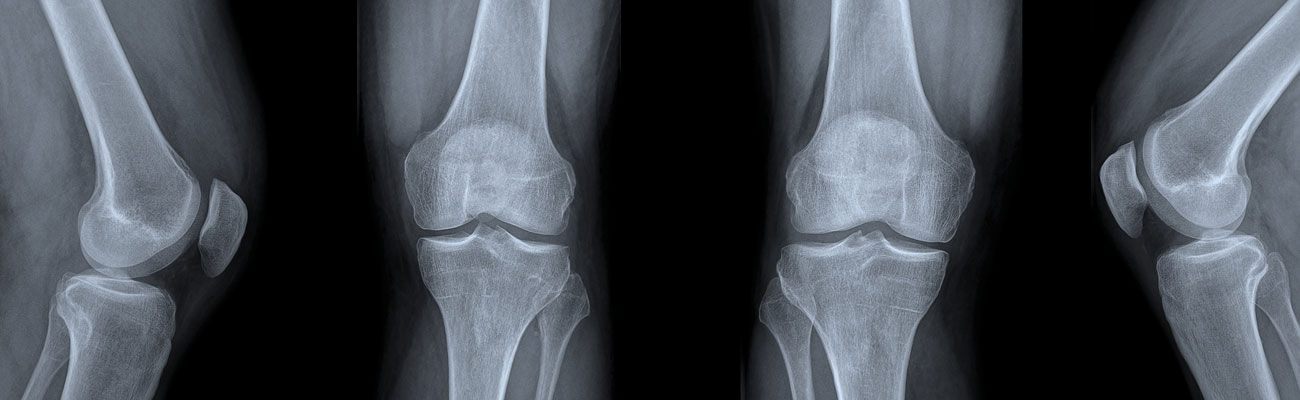

Arthrosetherapie

Arthrose bedeutet übersetzt Gelenkverschleiß. Im Laufe des Lebens kann mit hoher Wahrscheinlichkeit das ein oder andere Gelenk von Arthrose betroffen sein.

Arthrose entsteht in erster Linie altersbedingt. Weitere Ursachen sind zum Beispiel ein Übermaß an Belastung, angeborene oder traumatisch bedingte Fehlstellungen oder entzündliche Gelenkerkrankungen aus dem rheumatischen Formenkreis.